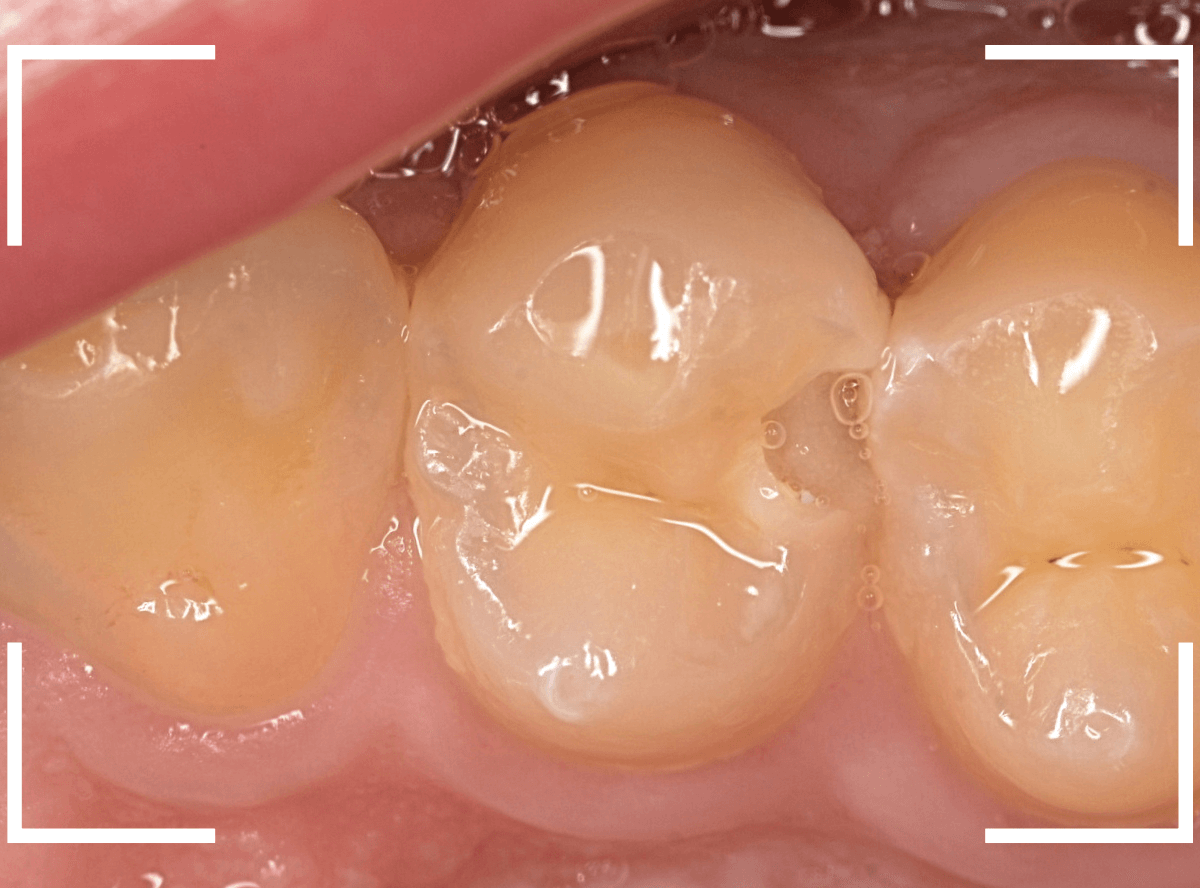

Case.22 痛みはないけど、歯のすきまから大きな虫歯

上の小臼歯の間が虫歯になっていた患者さんです。

症状はありませんし、見た目からも虫歯があるかはわかりませんでした。

レントゲン写真で確認します。

治療を開始します。

少し削ると、中からすぐに虫歯が出てきました。

全ての虫歯を除去しました。

レントゲン写真からある程度確認出来ましたが、歯の神経スレスレまで虫歯が進行していました。

ここまで虫歯が進行していても、全く症状を感じない事も多いです。

そして、ある時急に痛みを感じるのです。

虫歯は急に進行しません。

治療後の定期検診で確実に食い止めましょう。